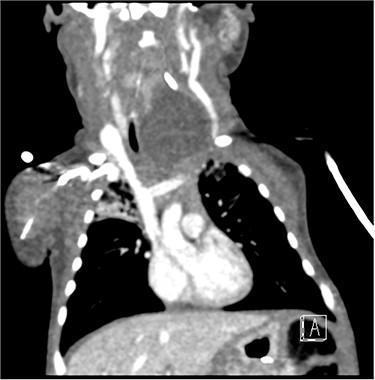

Sagittal barium sallow illustrating the presence of an oesophageal diverticulum, filled with contrast on swallowing.

At age 8 months, the patient was admitted to hospital from clinic due to worsening stridor. She underwent a further MLB that once again illustrated a cyst. An ultrasound scan was performed intraoperatively to aid with emptying of the cyst, and an incidental finding of a connection between the cyst and the cricopharyngeal region was identified, in keeping with a diagnosis of an oesophageal diverticulum. This was later confirmed on a barium swallow study (Fig. 4). Following the MLB, the patient remained clinically stable; the stridor resolved.